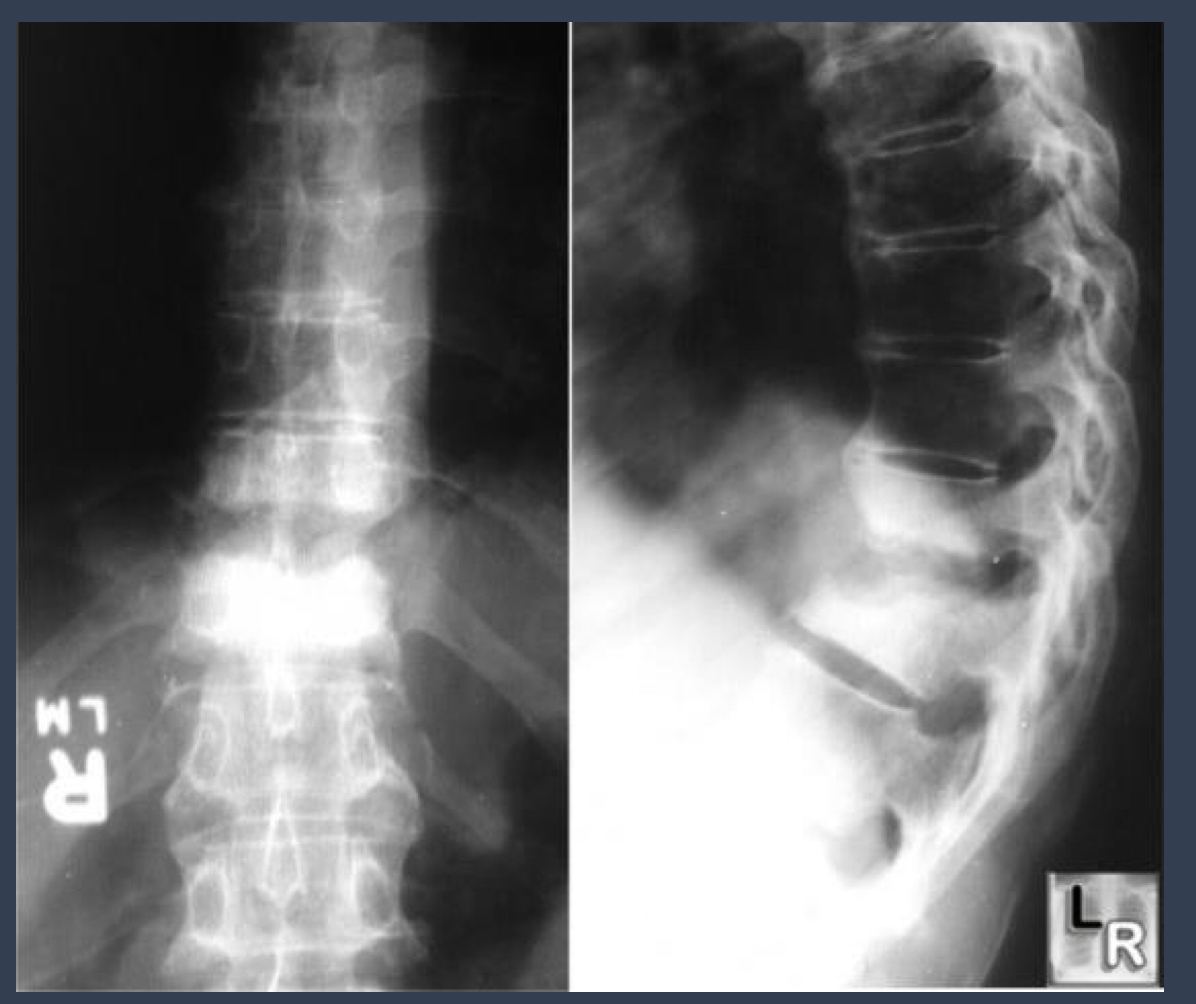

what condition is this?

severe **disc space narrowing** endplate destruction (hazy, irregular)

Condition: Spondylodiscitis

infection involving disc and adjacent vertebral body

what is this?

spondylodiscitis